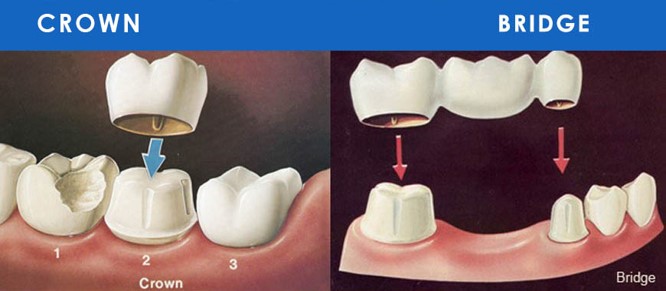

陶瓷崁體、冠塊體

當患者牙齒抽過神經,或蛀洞過大時,傳統上會在真牙外層套上假牙,保護脆弱的牙齒;但假牙對牙齒的修磨過多,已非最理想的治療方式。

陶瓷嵌體,也就是3D齒雕,是利用強度與顏色皆和真牙相仿的陶瓷,如拼圖般補上牙齒的缺損處,不但恢復牙齒強度,也能為患者保留更多的齒質。